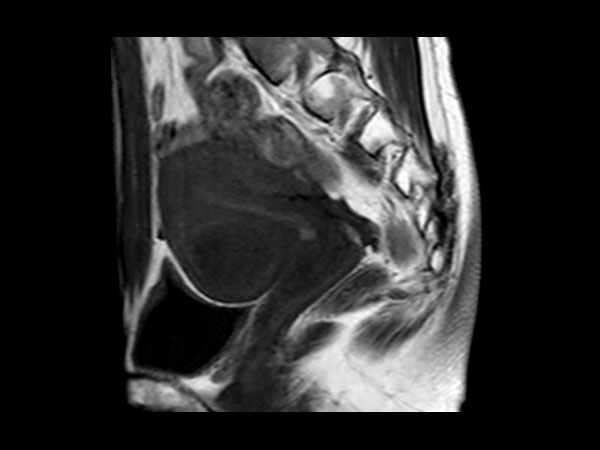

Female Pelvis

Toyonaka Hospital, Japan

• Clinical Application